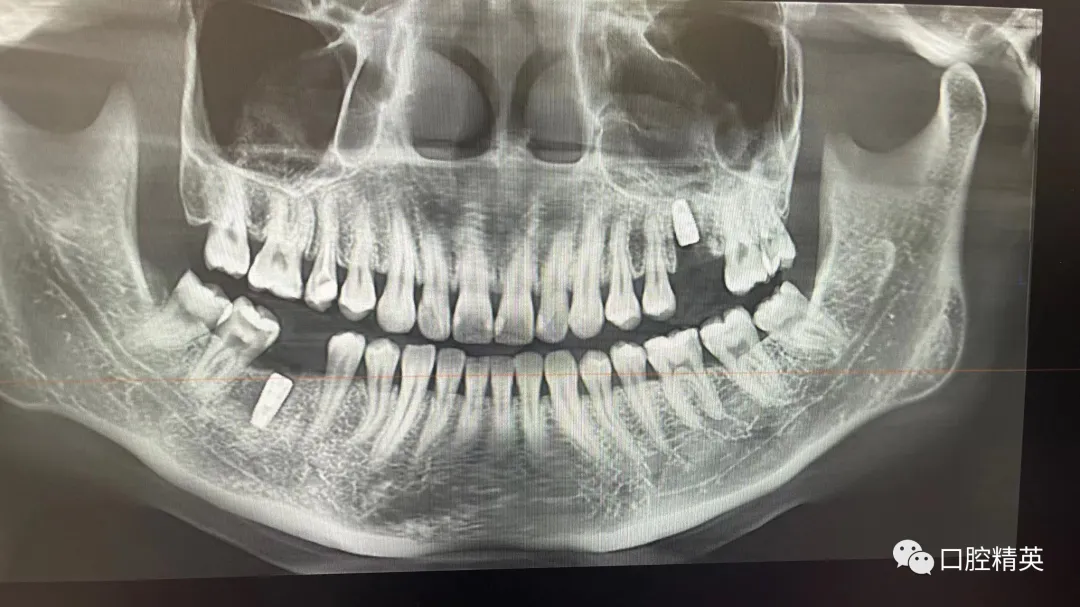

7、种植影像学分析;可以获得骨高度 ,骨宽度信息 ,甚至可以模拟种植体植入位点

六、学员回家后部分病例